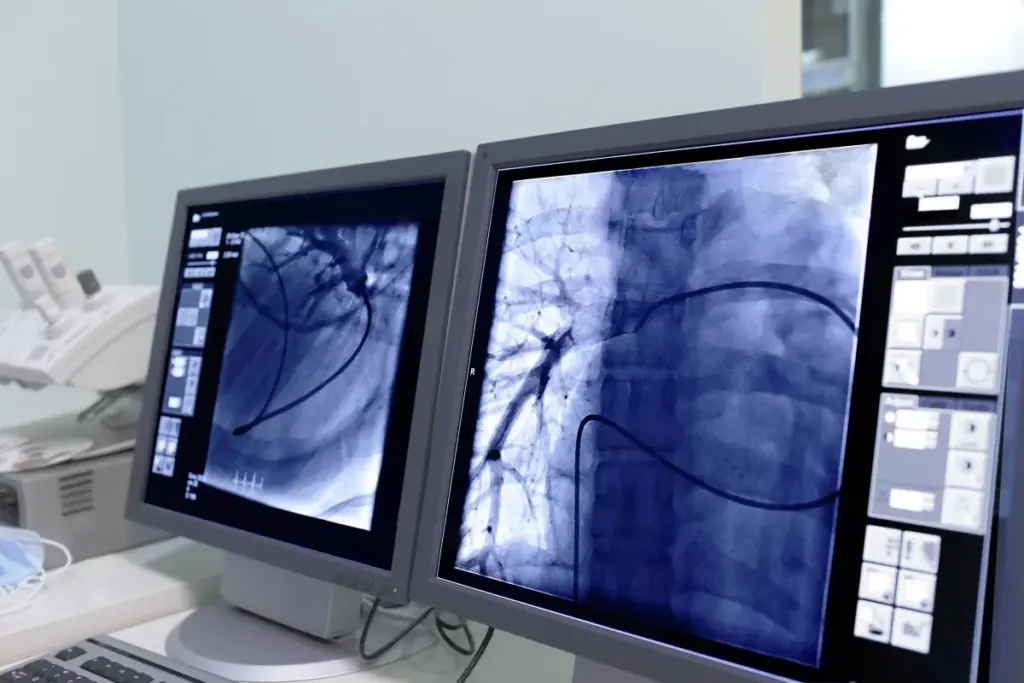

Interventional radiology is a fast-growing field. It offers new ways to treat many medical issues. IR uses imaging to guide procedures that are less invasive. This means less risk and quicker recovery times than traditional surgery.

Interventional radiology is a medical field that uses imaging like X-ray and MRI. It guides procedures that are both for diagnosis and treatment. IR covers a wide range, from vascular interventions to non-vascular procedures like biopsies.

Common Types of IR Procedures

IR procedures include vascular interventions like angioplasty and stenting. They also include non-vascular procedures like biopsies and tumor treatments. These are designed to be less invasive, reducing risks and promoting faster recovery.

• Vascular interventions: angioplasty, stenting, and embolization.

• Non-vascular procedures: biopsies, drainages, and tumor treatments.